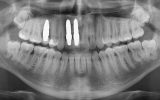

One of the standout contributions of the seminar was the clinical poster presented by Nino Kneževič, featuring a patient treated at Center Hočevar.

The poster provided a clear and structured overview of the pre-, intra-, and postoperative stages of ceramic implant placement, illustrating:

the biological reasoning behind treatment decisions,

the dynamics of soft- and hard-tissue healing,

and the long-term functional and aesthetic outcomes achievable with ceramic implants.